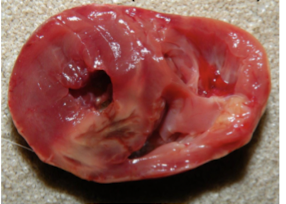

What is this change associated with, is it post mortem or antimortem? Is this common practice anymore?

• Intracardiac euthanasia used to be common with pentobarbitol. Solution can cause the solution to precipitate and look like mineralization. Know how euthanasia was administered.

What can indicate improper euthanasia technique when a cardiac stick has been prefomed to administer the euthanasia solution?

Coagulative Necrosis of Myocardium